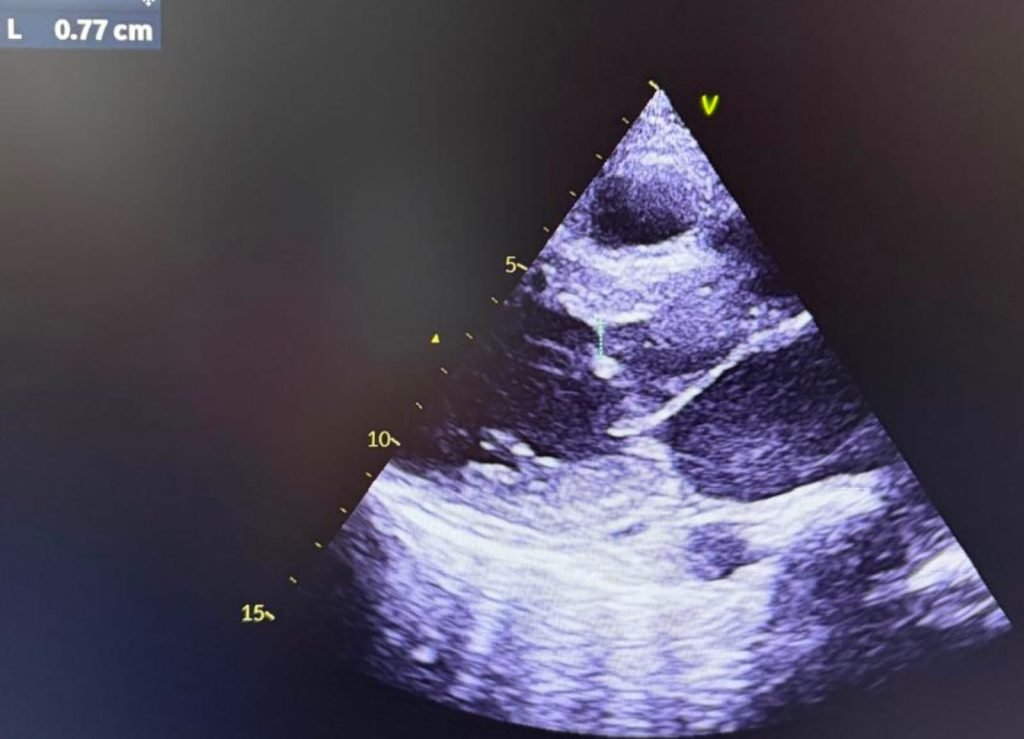

Echocardiographic Findings

Images and videos:

| Echocardiography revealed: |

| Features consistent with hypertrophic cardiomyopathy |

| Systolic anterior motion (SAM) of the posterior mitral leaflet (PML) |

| Dynamic LVOT obstruction |

| LVOT mean pressure gradient: |

| 14 mmHg at rest |

| 20 mmHg on Valsalva |

| Mild subaortic obstruction |

| Mild pulmonary arterial hypertension |

| Right ventricular diastolic dysfunction |

| Mild pericardial effusion |

Notably, SAM involved the posterior mitral leaflet — an uncommon variant — rather than the classical anterior leaflet SAM seen in obstructive HCM.

The four-chamber echocardiographic view demonstrates biventricular involvement along with associated pericardial effusion. In this clinical context, cardiac MRI represents a crucial diagnostic investigation, providing comprehensive structural and tissue characterization.